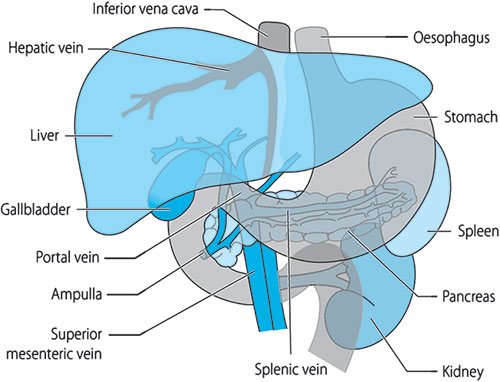

For convenience the abdominal cavity is divided into nine segments (Figure 1.1). These regions can be demarcated on an abdominal radiograph by drawing a horizontal line through the 9th ribs and the pelvic brim, and two vertical lines from the centre of the costal cartilage of the 9th rib to the middle of the inguinal ligament. The organs (Figure 1.2) contained in these segments are as follows:

- Right hypochondrium: gallbladder, right lobe of liver, duodenum, hepatic flexure of colon, upper pole of right kidney and pancreatic head

- Epigastrium: stomach, pancreatic body, left lobe of liver

- Left hypochondrium: spleen, splenic flexure of colon, and upper pole of left kidney

- Right lumbar region: ascending colon and right kidney

- Umbilical region: transverse colon, greater omentum and small bowel

- Left lumbar region: descending colon and left kidney

- Right iliac fossa: caecum, terminal ileum, appendix and ureter

- Hypogastrium: small intestine, bladder and gravid uterus

- Left iliac fossa: sigmoid colon, ureter and small bowel.